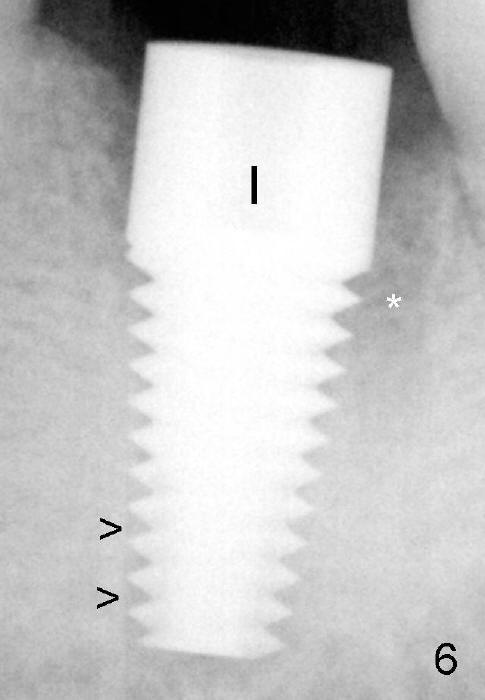

An implant with the same dimension (7x17) mm is placed with insertion torque more than 60 Ncm (Fig.6 I). *: remaining distal socket